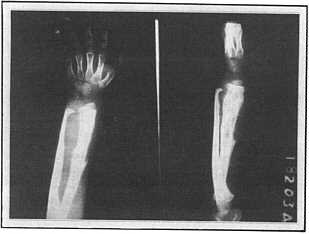

Photo 3: Initial X-ray of left arm from a 3 year

old girl

diagnosed with Ewing's sarcoma of the bone

(August 17,1970) |